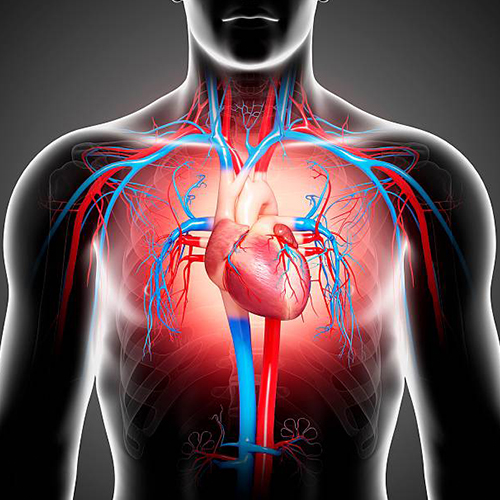

Анатомия здорового сердца: фотографии и иллюстрации